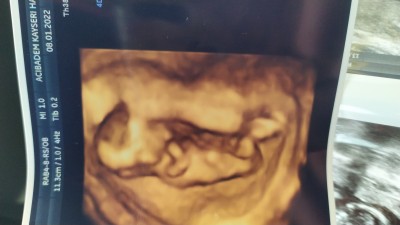

image

13+2 burda  dün gitim ama söylemedi doktor:(